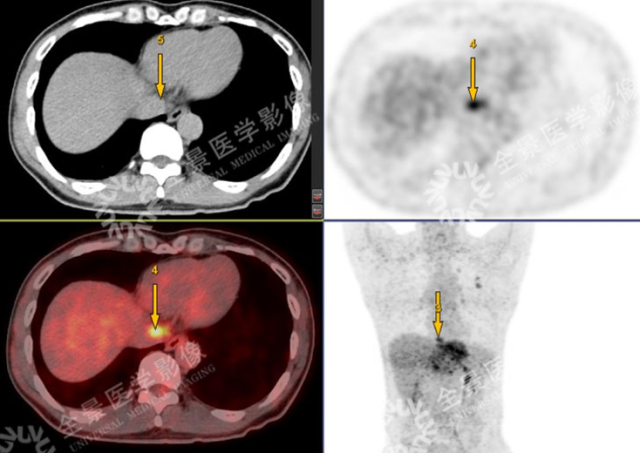

PET 示:腔静脉裂孔处结节 FDG 摄取增高;

CT 示:无明显异常密度影。

怀疑:腔静脉癌栓?后心膈角区淋巴结?

确诊:腔静脉癌栓